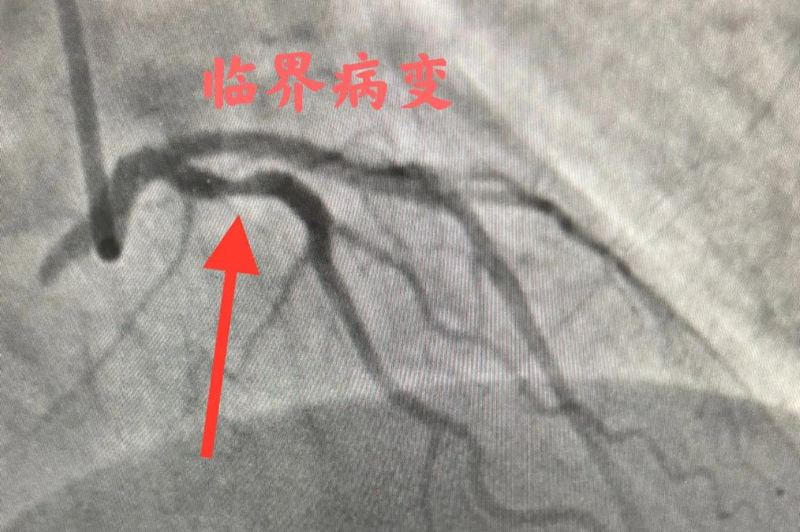

患者及家属表示接受冠脉造影检查。12月13日,于主任医疗团队在为患者行冠脉造影检查过程中发现患者冠脉狭窄70%左右,回旋支近段处于临界病变。

临界病变医生无法用肉眼进行准确判断,需要进一步科学判断狭窄范围是否会引起心肌缺血,方能决定是否需要植入支架。于主任与患者家属沟通,建议行FFR检查明确诊断,家属表示同意。

于主任使用医院新引进的压力微导管为患者完成FFR检查。检查结果为0.98,高于临界值0.8,明确患者无需行心脏支架治疗。